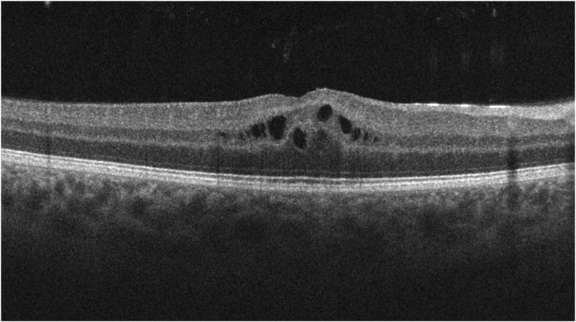

L'oedème maculaire cystoïde (OMC) est une affection rétinienne assez fréquente, et qui entraîne une baisse de la vision En fonction de son étiologie, on assistera à une disparition de cet oedème ou bien, au contraire, à une persistance des lésions L'OMC correspond à la formation de cavités (logettes) au sein de la couche rétinienne plexiforme externe (couche des fibres de Henlé), et/ou dans la couche granuleuse interne. Translations in context of "cystoïde" in FrenchEnglish from Reverso Context Des cas d 'œ dème maculaire cystoïde ont été rapportés avec GANFORT. Introduction L’œdème maculaire post opératoire est une complication bien connue après chirurgie de la cataracte, mais il peut compliquer bien d’autres chirurgies endoculaires et d’autres traitements (chirurgie extraoculaire et traitements au laser).

œdème maculaire cystoïde, médicament, toxicité zzzzzz * Service d’Ophtalmologie, Hôpital Erasme, Université Libre de Bruxelles, Bruxelles Bull Soc belge Ophtalmol,304, 7176, 07 71 DÉFINITION L’œdème maculaire cystoïde (OMC) est une accumulation maculaire de liquide avec formation. Définition du terme Oedème maculaire cystoïde L'oedème maculaire cystoïde est une affectionrétinienne assez fréquente, correspondant à la formation, au sein de la rétine, de cavités, ou logettes, disposées en rayons de roue Cette affection est responsable de troubles de la vision à type de diminution de l'acuité visuelle et parfois de métamorphopsies (vision ondulée des lignes droites) ou de scotomecentral. Dr Sébastien Olivier, ophtalmologiste, Hôpital MaisonneuveRosemont, nous parle de l'œdème maculaire, une complication à l'œil Pour en savoir plus wwwdiab.

Œdème maculaire cystoïde (CME) L'œdème maculaire cystoïde ou CME, est un trouble indolore qui affecte la rétine centrale ou la macula Résultats Plusieurs zones de liquide ressemblant à des kystes (cystoïdes) apparaissent dans la macula. Un œdème maculaire peut entraïner une baisse d’acuité visuelle centrale supplémentaire L’angiographie à la fluorescéine et/ou la tomographie par cohérence optique permet de détecter la présence d’un œdème maculaire chez 10 à % des patients atteints de rétinite pigmentaire (RP). Mie maculaire et des remaniements pigmentés rétrofovéaux L’œdème maculaire est fréquemment cystoïde, en particulier dans les formes non ischémiques Certaines occlusions veinulaires proches de la fovéa sont responsables d’un œdème maculaire et ne doivent pas être confondues avec une anastomose rétinocho.

L'œdème maculaire est parfois appelé œdème maculaire cystoïde pour préciser que l'accumulation de liquide s'effectue dans des petites cavités (logettes) à type de kystes. 1 retina 18 oct;38(10)7380 doi /iae acute pseudophakic cystoid macular edema imaged by optical coherence tomography angiography. œdème maculaire cystoïde Voici une complication de la chirurgie de la cataracte, de gravité moyenne, appelée "œdème maculaire cystoïde", qui correspond à une inflammation de la macula (il serait correct de baptiser ce syndrome "maculite", mais ce terme n'est pas consacré par l'usage) Sous le trait rouge vertical, la macula (normalement noire sur ce cliché d'angiographie à la fluorescéine) est soufflée de logettes pleines d'œdème, qui dessinent comme une couronne de pétales.